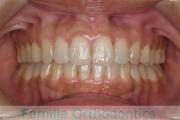

歯並びを治したいということで来院されました。下あごがやや右側に偏位して後退している、上顎前突(出っ歯)でした。上下左右から小臼歯を抜歯して、歯科矯正用アンカースクリューを併用したマルチブラケット法にて治療を行いました。約2年、24回の来院をしていただきました。

下顎の後退はいびきなどの上部気道の障害が出やすいと考えられます。